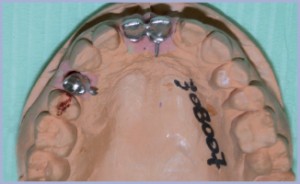

- Fig. 8 – Impronte

- Fig. 9 – Sovrastruttura protesica